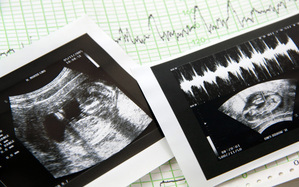

妊娠5ヶ月のエコー(超音波)写真